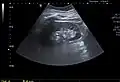

-

Renal ultrasonography of a simple renal cyst with posterior enhancement. -

Renal cyst as seen on abdominal ultrasound -